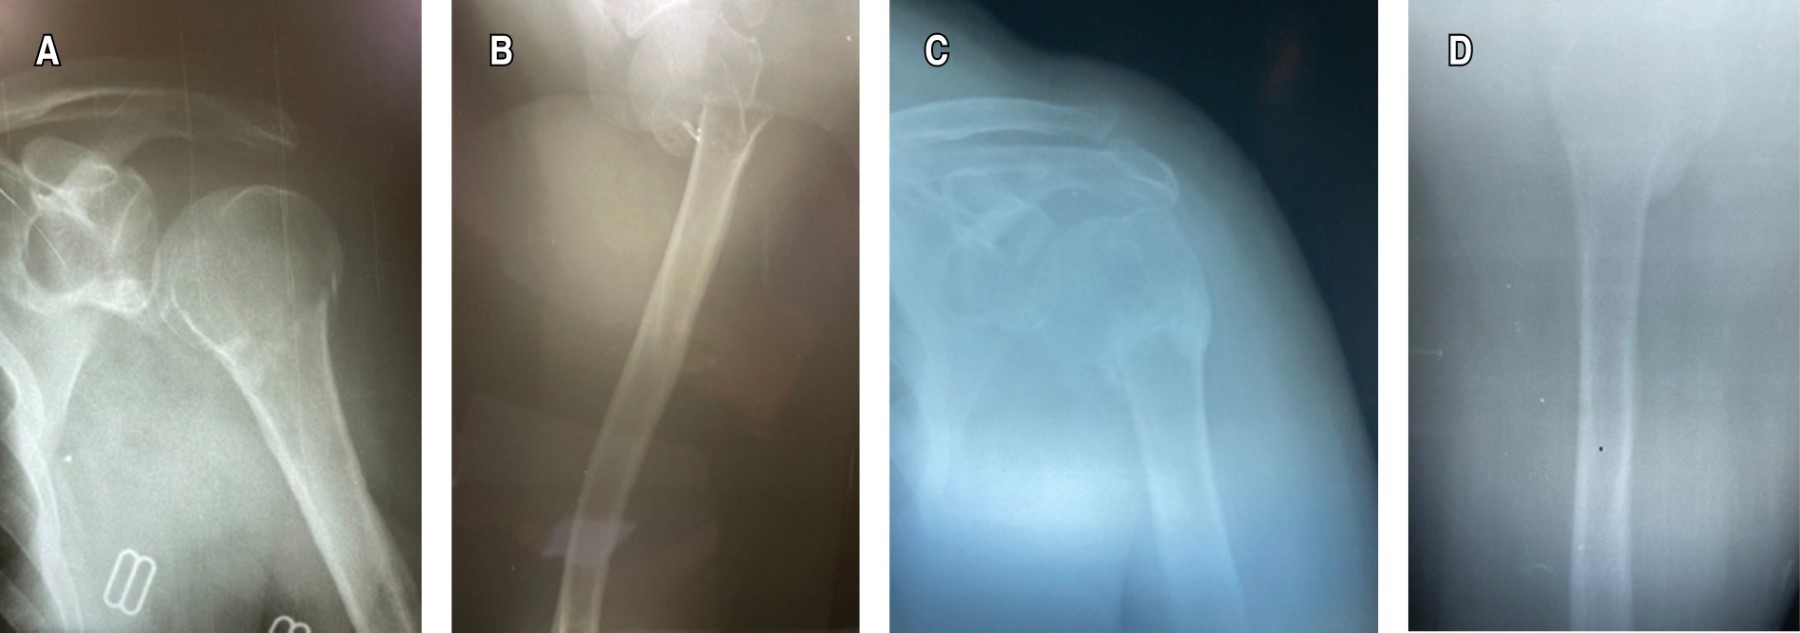

Early mobilization in the conservative management of proximal humeral fractures. A real risk?

Early mobilization is the mainstay of conservative management of proximal humerus factures. In Mexico, the immobilization time is usually 3-4 weeks, followed by rehabilitation process, for fear of the risk of complications such as non-union, despite the fact that research supports early mobilization for a better patient prognosis. Objective: To determine if early mobilization, on the seventh day of immobilization, brings radiological bone consolidation and early positive functional results in Mexican patients with Neer II proximal humerus fracture. Material and methods: This is a prospective case report of 3 patients > 50 years with a diagnosis of Neer II proximal humerus fracture, they were immobilized for seven days with subsequent early mobilization, the Constant-Murley Functional Scale, DASH Questionnaire, and Montoya radiological scale at the first, second and third month of evolution. Results: Patient 1. First month Constant Murley 26, DASH 64.1, Montoya GII, second month Constant-Murley 67.35, DASH 32.5, Montoya GIII, third month Constant-Murley 98, DASH 2.5, Montoya GIV. Patient 2. First Month Constant-Murley 44, DASH 33.3, Montoya GII, second month Constant-Murley 59.35, DASH 39.16, Montoya GIII, third month Constant-Murley 94, DASH 4, Montoya GIV. Patient 3. First month Constant-Murley 38, DASH 57.5, Montoya GII, second month Constant-Murley 67.62, DASH 10.83, Montoya GIII, third month Constant-Murley 96, DASH 5.75, Montoya GIV. Conclusion: Early mobilization in Mexican patients with Neer II proximal humerus fracture brings early excellent radiological and functional results if the patient is followed appropriately.

Figure 2

Figure 3

Figure 4

Figure 5

Figure 6

Figure 7

Figure 8

Figure 9

Figure 10